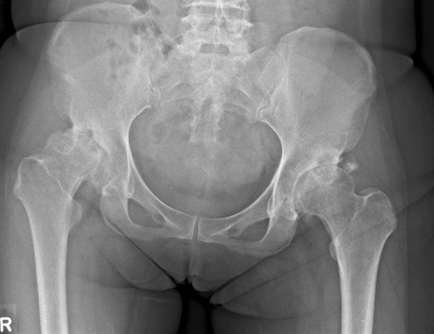

Stages of Hip Osteoarthritis

OA progresses through four stages:

- Stage 1 (Early): Minor cartilage wear with no pain; often undiagnosed.

- Stage 2 (Mild): Bone spur growth; occasional stiffness or pain after activity.

- Stage 3 (Moderate): Cartilage erosion becomes noticeable, causing frequent pain and limited mobility.

- Stage 4 (Severe): Cartilage loss is extensive, leading to bone-on-bone contact, chronic pain, joint deformity, and potential femoral head deformation (loss of the ball-shaped structure of the hip joint).

When is Total Hip Replacement Needed?

Total hip replacement (THR) becomes necessary when the joint damage is irreversible and conservative or regenerative treatments no longer provide relief. Key indicators for THR include:

- Bone-on-Bone Contact: Advanced cartilage loss (Stage 4 OA) confirmed by X-rays or MRI.

- Femoral Head Deformity: Structural damage to the femoral head (the "ball" of the hip joint), often due to avascular necrosis (bone death), severe OA, or congenital conditions like hip dysplasia. Deformity disrupts smooth joint movement, causing grinding, instability, and irreversible joint damage.